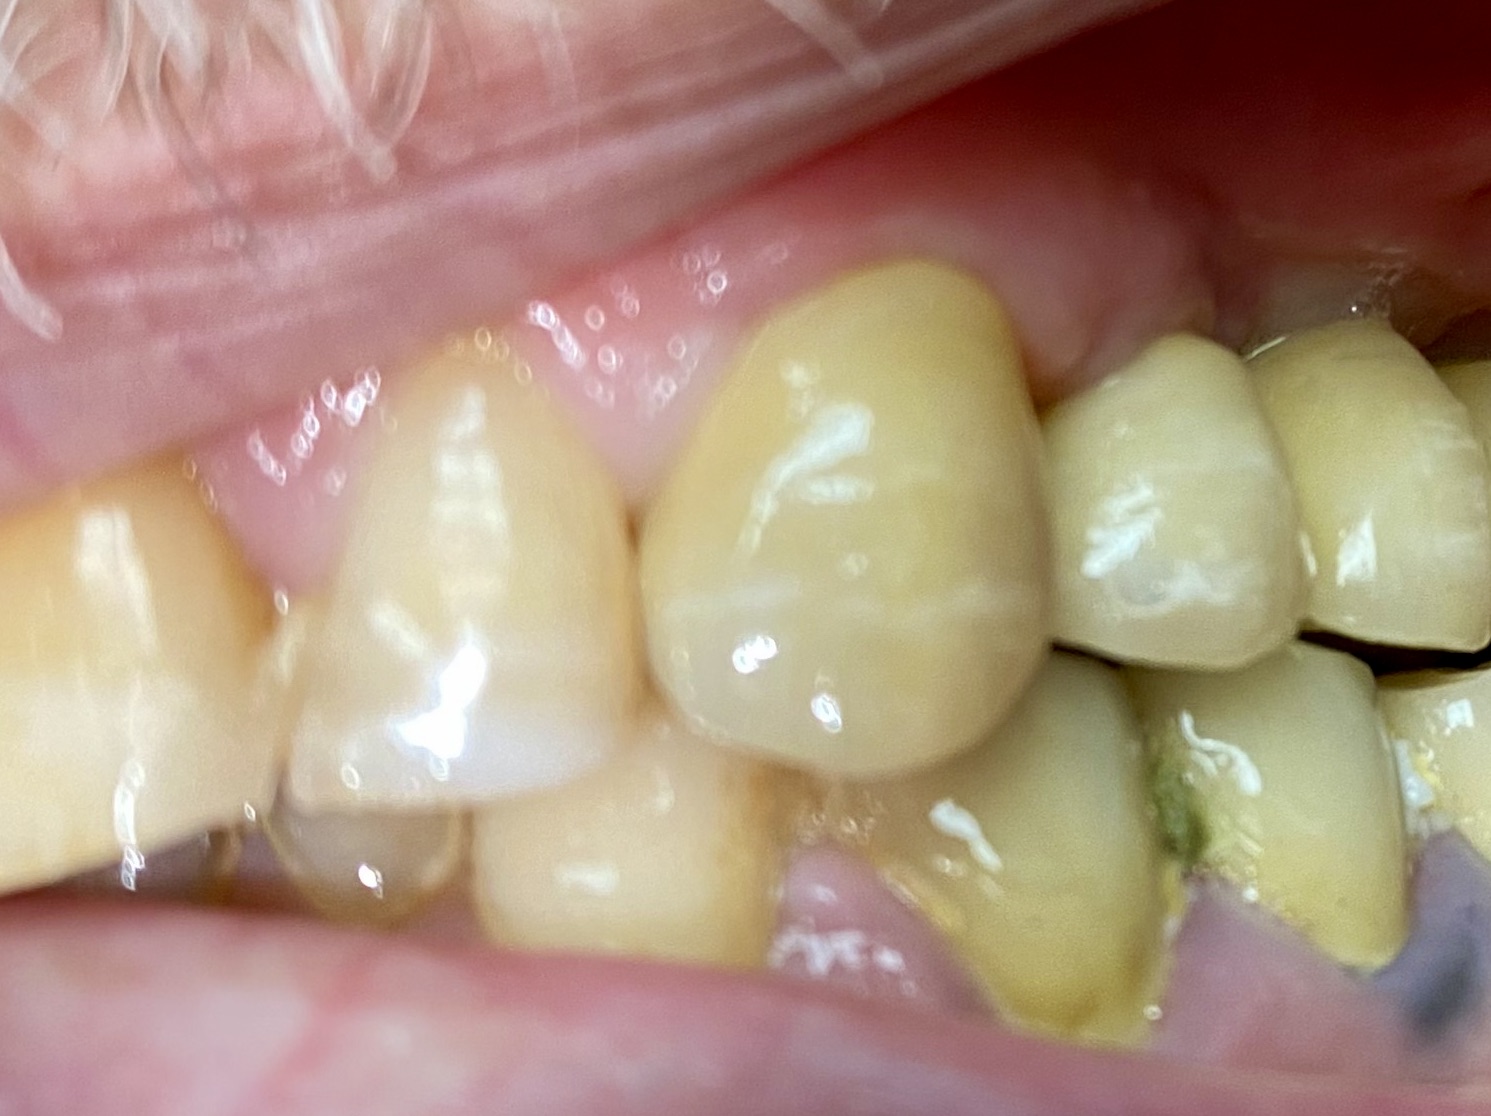

כתר דנטלי הוא טיפול דנטלי שיקומי פרוטתי, המשתמש בחומרים כמו זירקוניה או מתכת, מצופים בחרסינה, כדי לכסות או להחליף את חלק העליון של שן פגועה או מזויקה. הכתר נעשה למדידה מדויקת של השן המוקטנת בהשחזה והוא מותאם אישית על כל שן. הכתר משחזר במדוייק צורה , צבע ובגודל המתאימים ומותאם בצורה יציבה על השן, משפרות את המראה הקוסמטי של השן ומשפרות את תיפקודי האיבר הפגוע, מגבול החניכיים עד לשטח הלעיסי